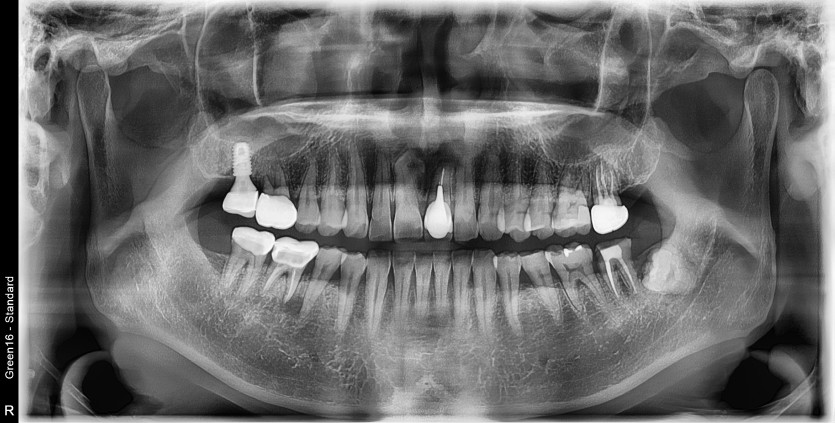

#38 사랑니 발치

#38 사랑니 발치 구강 외과 전문의가 당일 발치했습니다.